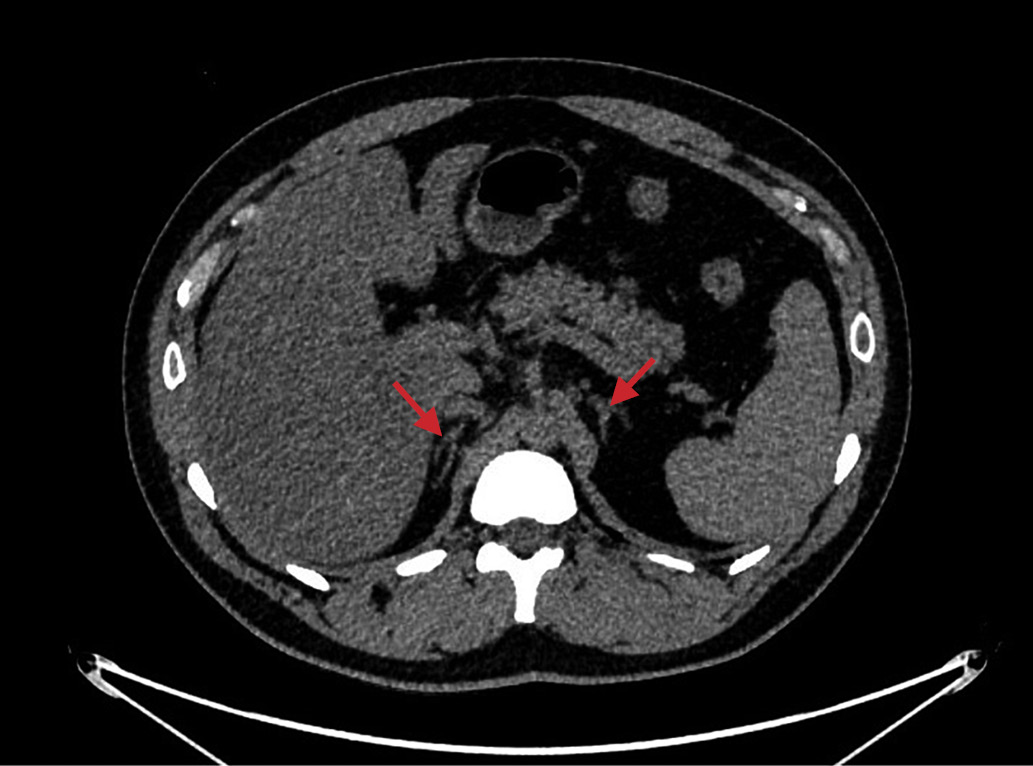

1. Рисунок 1. Мультиспиральная компьютерная томография надпочечников без контрастирования пациента №1.

Посмотреть (125KB)